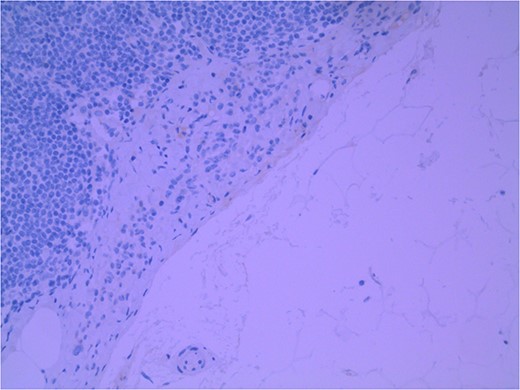

Lymph node specimens were sent for haematoxylin and eosin (H&E) staining (Fig. 3) and IHC analysis. The sections showed mild reactive changes and benign intracapsular nevoid rests. IHC analysis showed that these cells were negative for HMB-45 (Fig. 4) and were positive for both Sox10 and p16 (Figs 5 and 6). Consensus at the Multidisciplinary Team Meeting was that the appearance was in keeping with benign naevoid rests as opposed to melanoma deposits, given the location of the cells, morphology and immunohistochemistry. Surveillance was recommended.

Lymph node with IHC using HMB-45 stain, not staining subcapsular region melanocytic cells; × 200 magnification.

Several IHC stains are in use in the pathological interpretation of primary lesions and SLN biopsies. The antibody HMB-45 reacts with most melanomas. In a primary lesion, HMB-45 is immunoreactive with intraepidermal and superficial dermal components of benign nevi [14]. In a lymph node, however, benign nevoid cells are negative for HMB-45 and appear bland. A loss of HMB-45 expression has been reported in 20% of melanocytic metastasis, illustrating the need for further diagnostic testing [14]. Sox10 is a nuclear transcription factor that stains benign and malignant melanocytic cells. It indicates the extent of melanocytic spread but does not differentiate between benign nevi and metastatic melanoma [15]. Immunostaining for the tumour suppressor gene p16 differentiates between benign naevi and melanocytic metastases in the SLN. One study demonstrated positive nuclear and cytoplasmic p16 staining in all nevi (dermal and lymph node) and the absence of nuclear p16 staining in all but one melanoma metastasis [14]. No single stain is completely sensitive for melanocytic metastases, and a confident diagnosis relies upon cell location, morphology and multiple IHC techniques. SLN biopsy in the current patient demonstrated intracapsular melanocytic cells which stained negative for HMB-45, and positive for Sox10 and p16, in keeping with benign nevoid rests as opposed to metastatic melanoma.